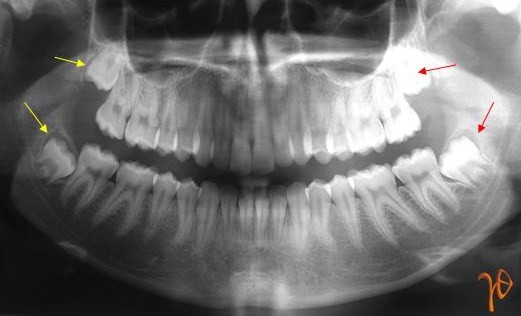

Προηγείται μια πανοραμική ακτινογραφία στην οποία αξιολογούνται η σχετική ανατομική θέση και η πιθανή παθολογία που μπορεί να συνοδεύει τους φρονιμίτες (Εικόνα 1).

Εικόνα 1. Πανοραμική ακτινογραφία: Με κίτρινα βέλη σημειώνονται οι δεξιοί άνω και κάτω φρονιμίτες και με κόκκινα βέλη οι αριστεροί.